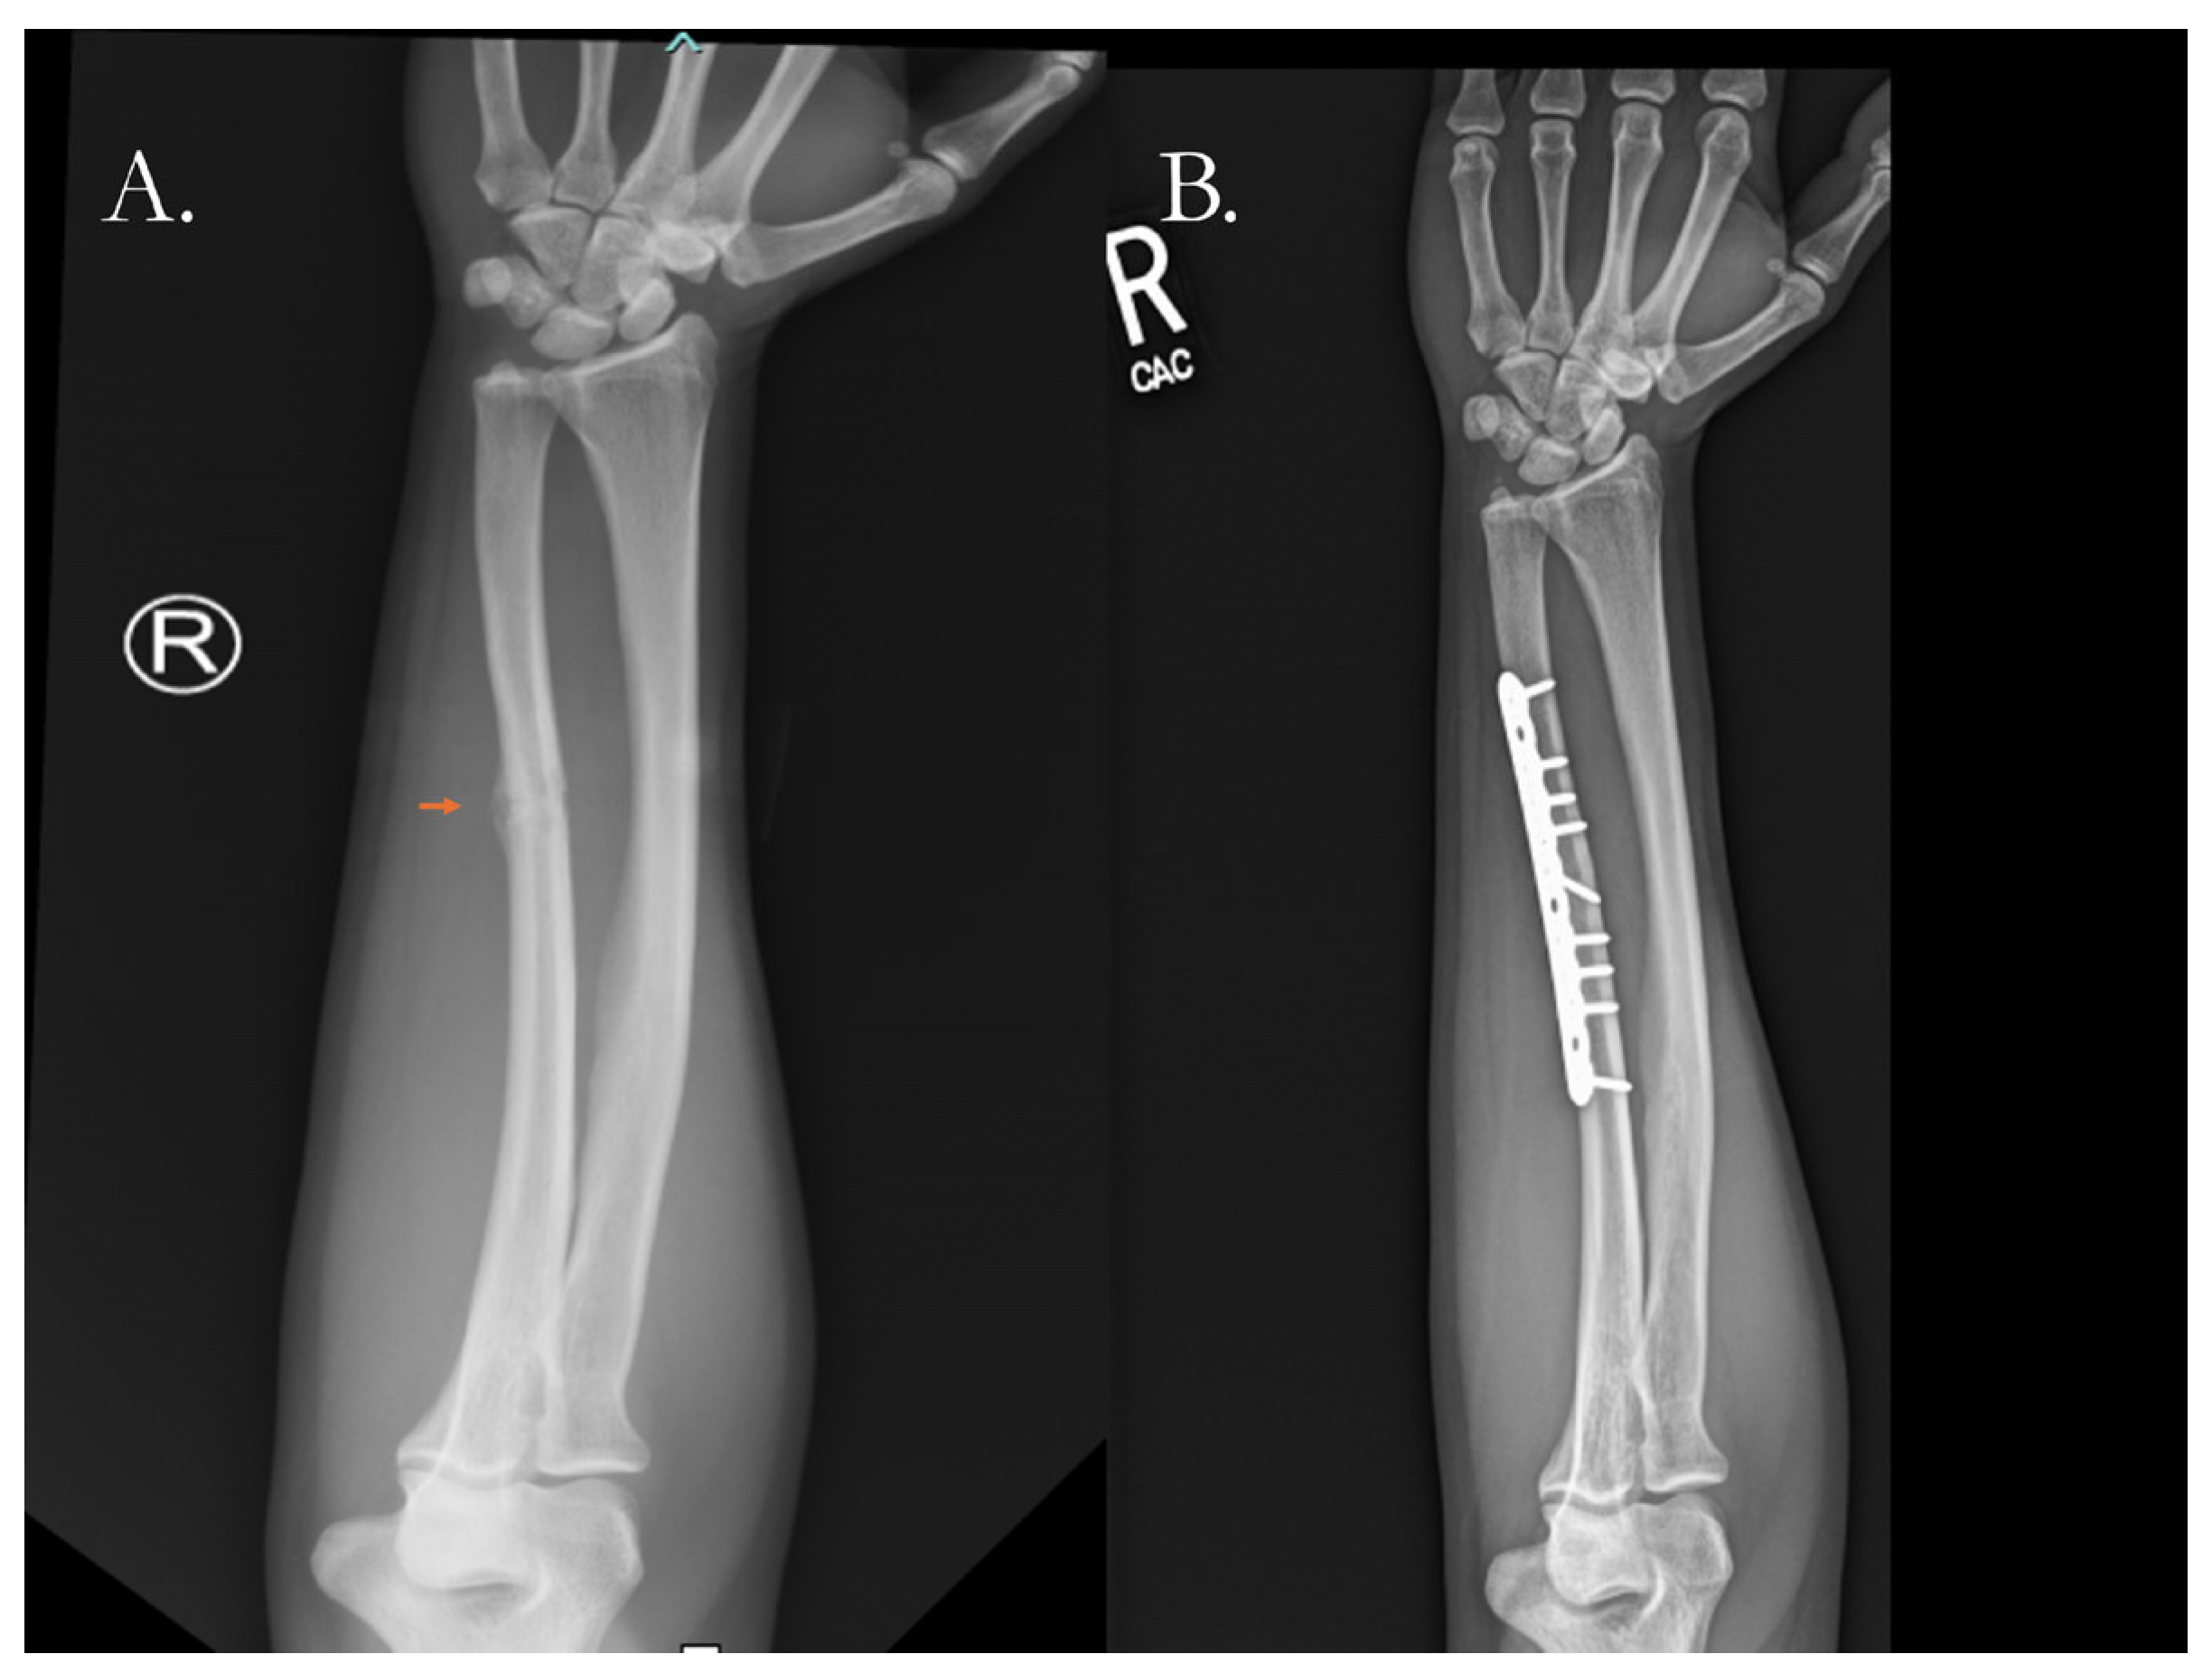

4.2.1. Traditional Surgical Approaches

- Mazzotta, A.; Stagni, C.; Rocchi, M.; Rani, N.; Del Piccolo, N.; Filardo, G.; Dallari, D. Bone Marrow Aspirate Concentrate/Platelet-Rich Fibrin Augmentation Accelerates Healing of Aseptic Upper Limb Nonunions. J. Orthop. Traumatol. 2021, 22, 21. [Google Scholar] [CrossRef]